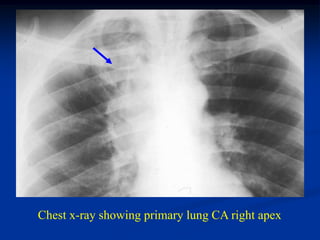

Case #1146

43 year male with

metastatic lung CA

to distal humerus

Lateral view

Chest x-ray showing primary lung CA right apex